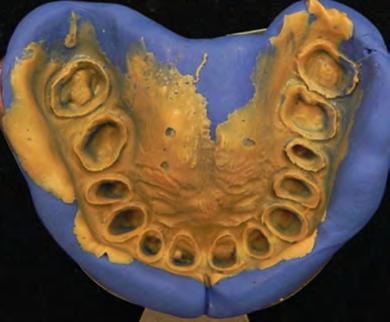

Figura 4. Aspecto de los pilares después de la aplicación de la radiofrecuencia. Arco dentario superior e inferior.

Se llevó a cabo la toma de impresiones con polivinilsiloxano regular (Virtual Putty de Ivoclar, Vivadent) y posteriormente con el material ligero (Virtual Putty Light) (Figura 5).

Se corrieron las impresiones con yeso Velmix tipo IV (Zhermack Elite Master) para obtener los modelos de trabajo y elaborar los troqueles utilizando ACCU-TRAC de la casa comercial Coltène Whaledent, el cual es un sistema de precisión para muñones desmontables, para ser utilizado en el encerado de cofias en cada uno de los muñones y la fabricación posterior de las coronas.

Figura 5. Impresiones para prótesis fija. Se observa perfectamente la terminación de los pilares PPF.